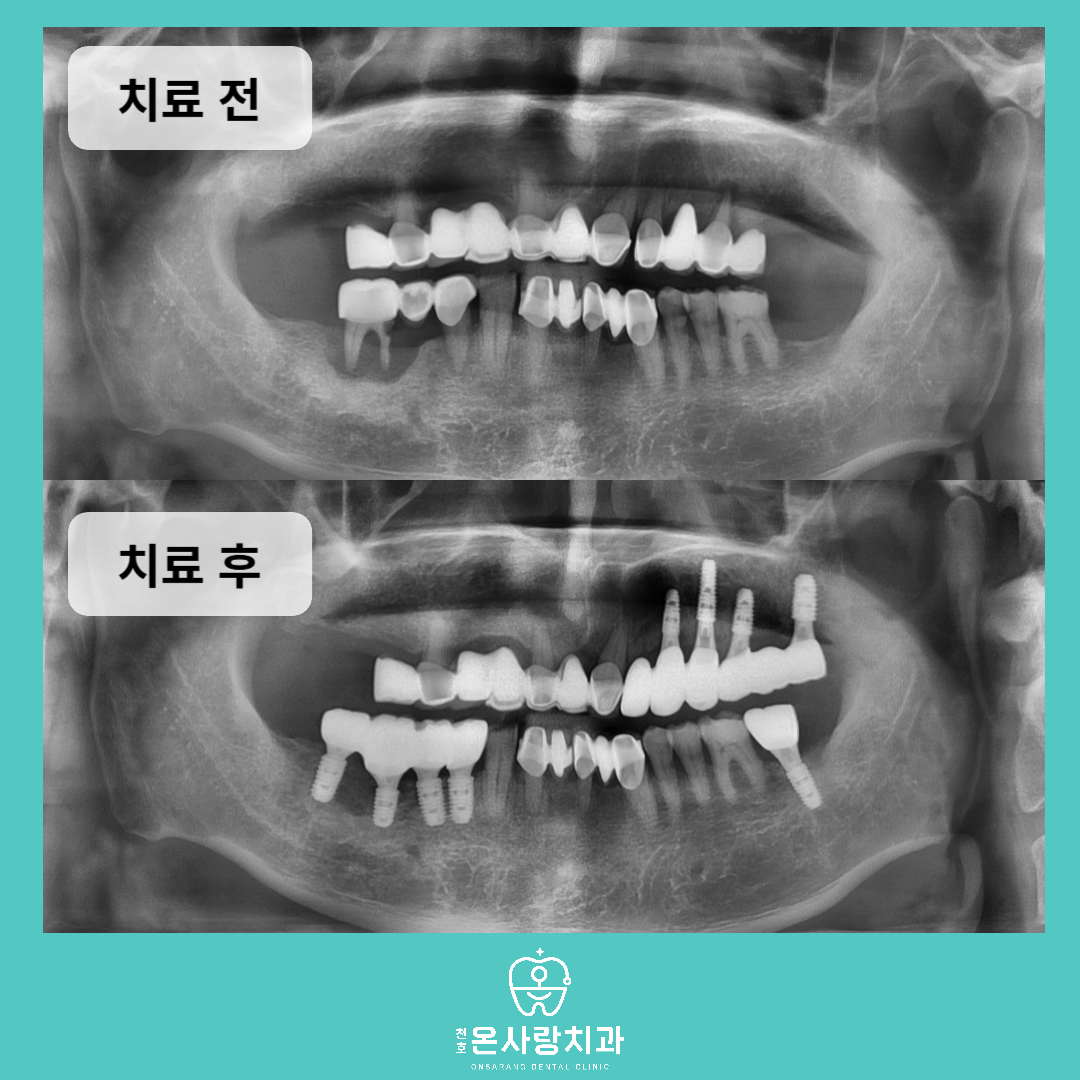

이번에 천호동치과 내원하신 환자분

역시 브릿지를 사용 중이었으나,

해당 부위의 치조골 파괴가 심각하여

음식물을 씹을 때 불편이 크고

치아의 동요도가 심한 상태였습니다.

간단한 문진과 구강내

검진 후 올바른 상태를 파악하기 위해서

전체 파노라마 x-ray를 촬영하였습니다.

아래와 위에 걸쳐서 양쪽의

브릿지 하방에 위치한

잇몸뼈들이 치아 주변을

따라서 상당히 파괴되어

거의 남아있지 않은 것을

볼 수 있습니다.

브릿지의 뒷 부분에 위치한 치아들에서

치조골의 파괴가 뚜렷하게 관찰되었으나

앞니에 연결이 되어있는 상태이고,

전체적으로 신경치료가 되어있지 않아서

불편함이 심각한 상황이었습니다.

브릿지를 커팅하거나 혹은 제거하여

현재 치아를 보존하는 치료로는

치료결과를 장담하는 것이 불확실하였고,

주변으로 남아있는 치조골

상태를 고려했을 때

발치를 통한 근본적

해결이 필요했습니다.

따라서 문제가 된 치아를

발치한 후 치조골 상태를 면밀히 확인한 뒤

충분한 적합성을 확보할 수 있도록

임플란트를 식립하였습니다.

발치를 진행한 부위와 상하의

대합관계를 고려하여

총 9개의 임플란트를 식립한 뒤

보철을 마무리하였습니다.